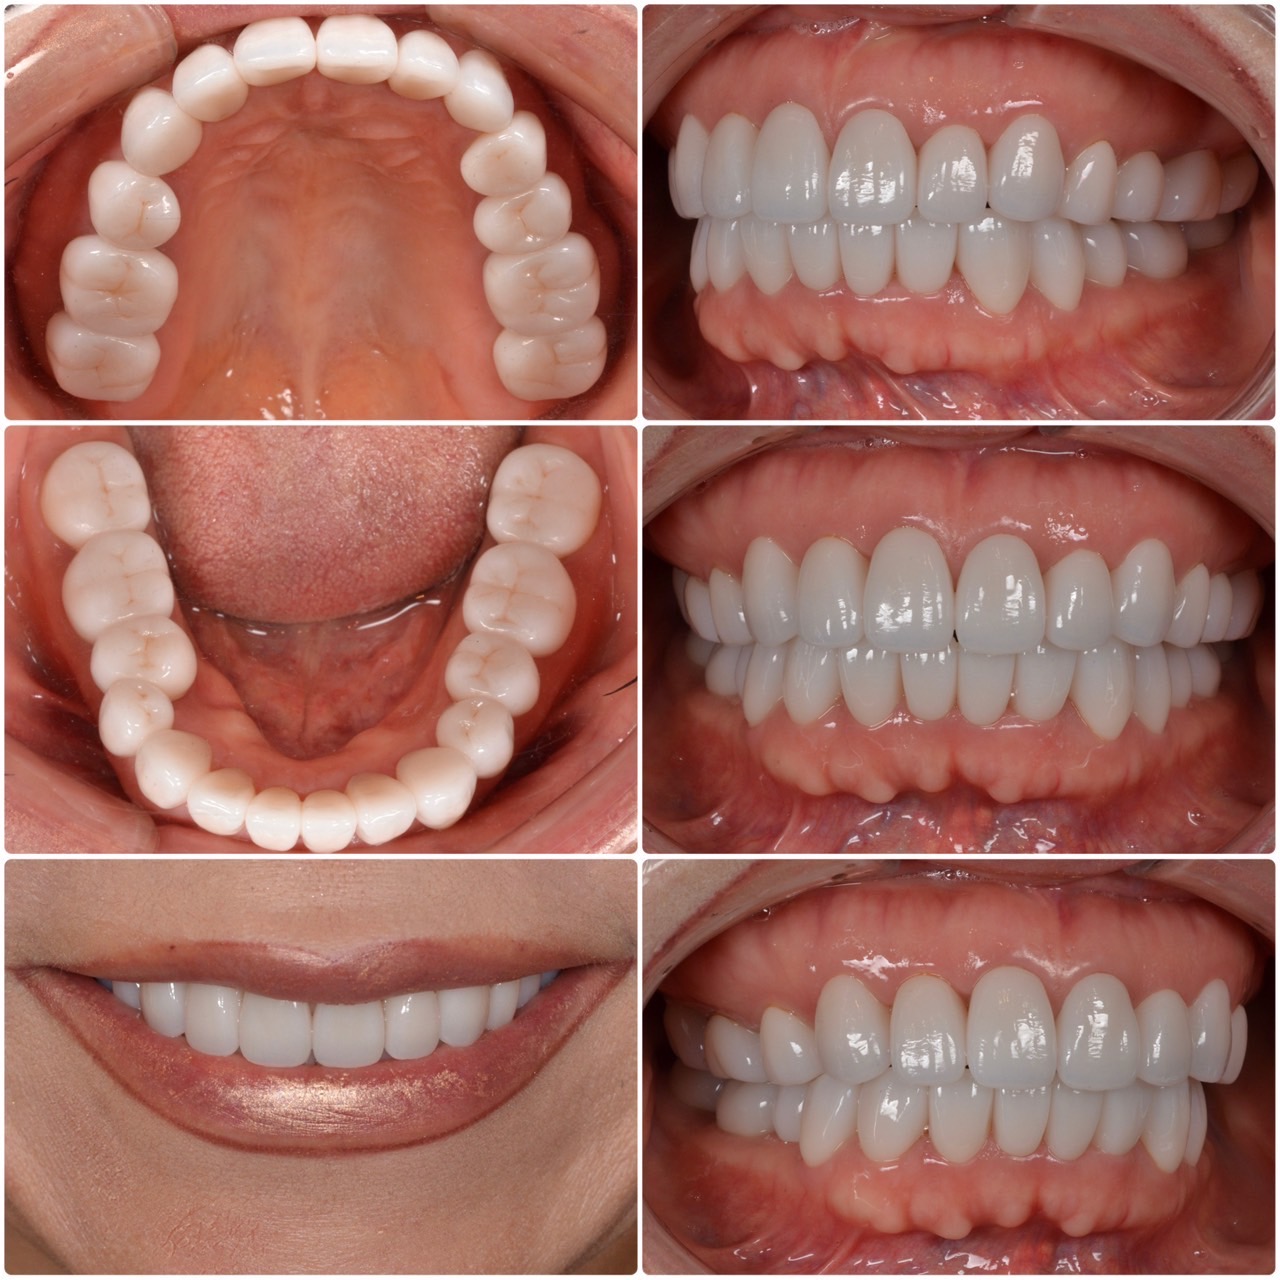

主訴・術前 歯を綺麗にしたい 診断の結果 術後の患者様の感想 気になっていたところがすべて治ったのでとても嬉しかったです。 自分の気になるところと先生がやったほうがいいと思うところと様々な意見が聞けたので勉強にもなりました。 また、定期検診… 続きを読む -

主訴・術前 セラミック希望 術後の患者様の感想 痛みが苦手で治療を何年も先延ばしにしていました。 歯医者も数十年ぶりで、歯周治療なども併用して歯も歯茎もとても綺麗に生まれ変わり、本当に感動しています。 今後はメンテナンスにもしっかりと通い、… 続きを読む -